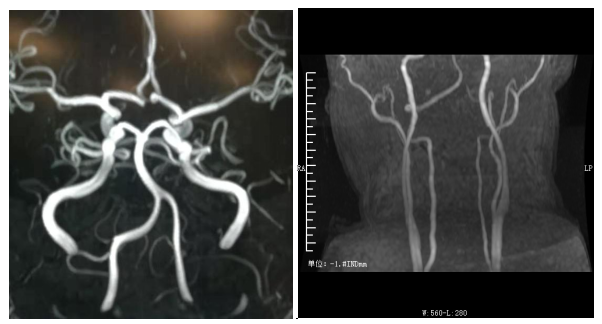

头部MRA正常 颈部MRA左侧椎动脉纤细